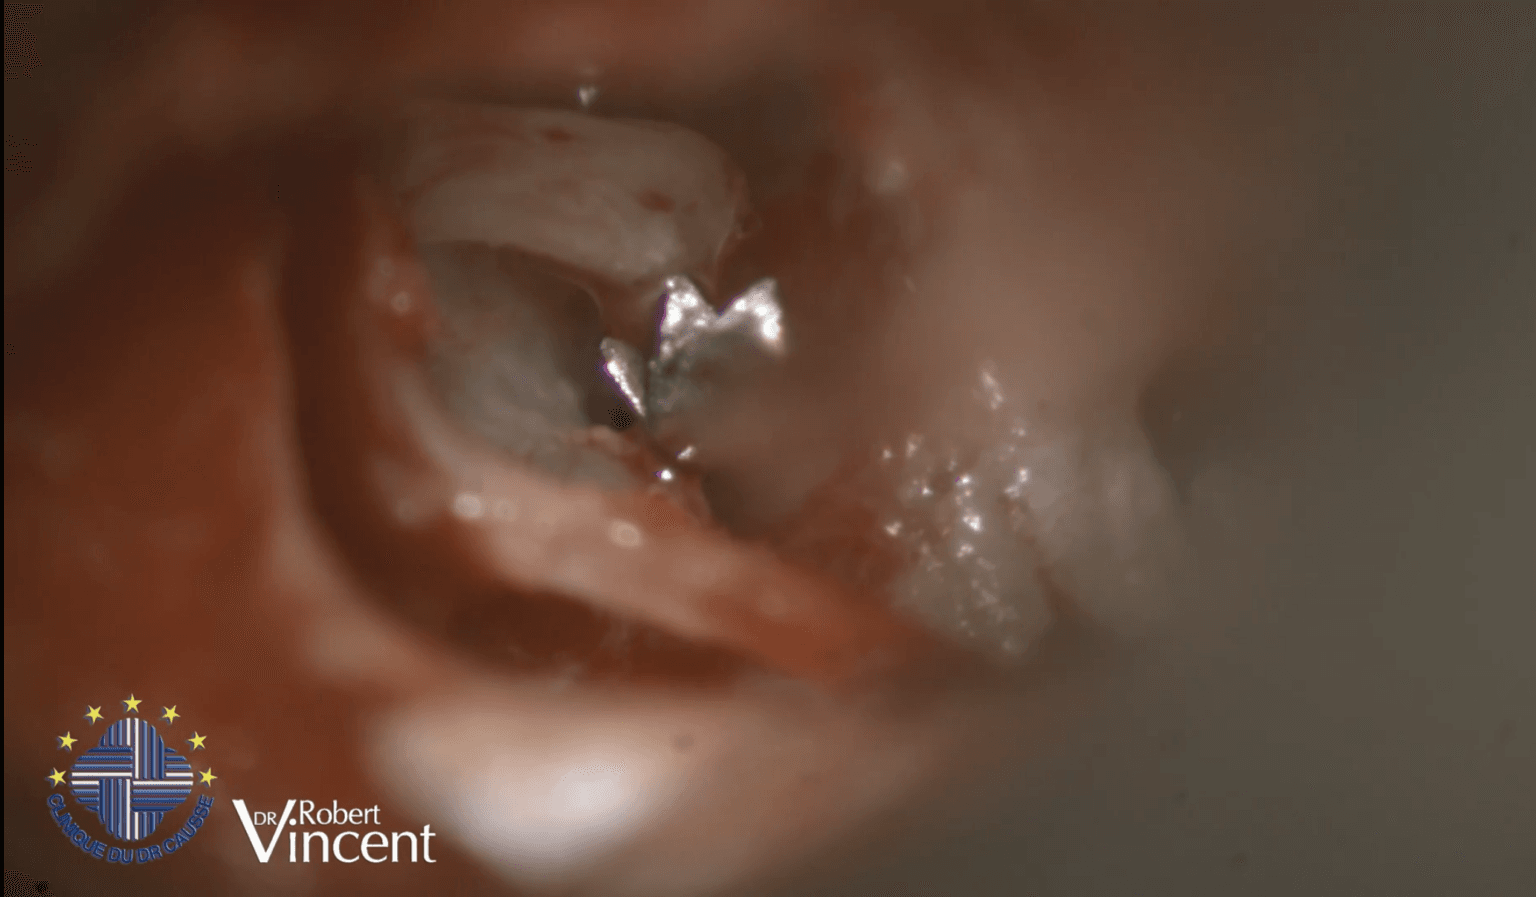

Estapedotomía: ventana oval estrecha y dehiscencia del VII par

El Dr. Robert Vincent realiza una estapedotomía compleja en una ventana oval extremadamente estrecha, asociada a una dehiscencia severa del nervio facial.